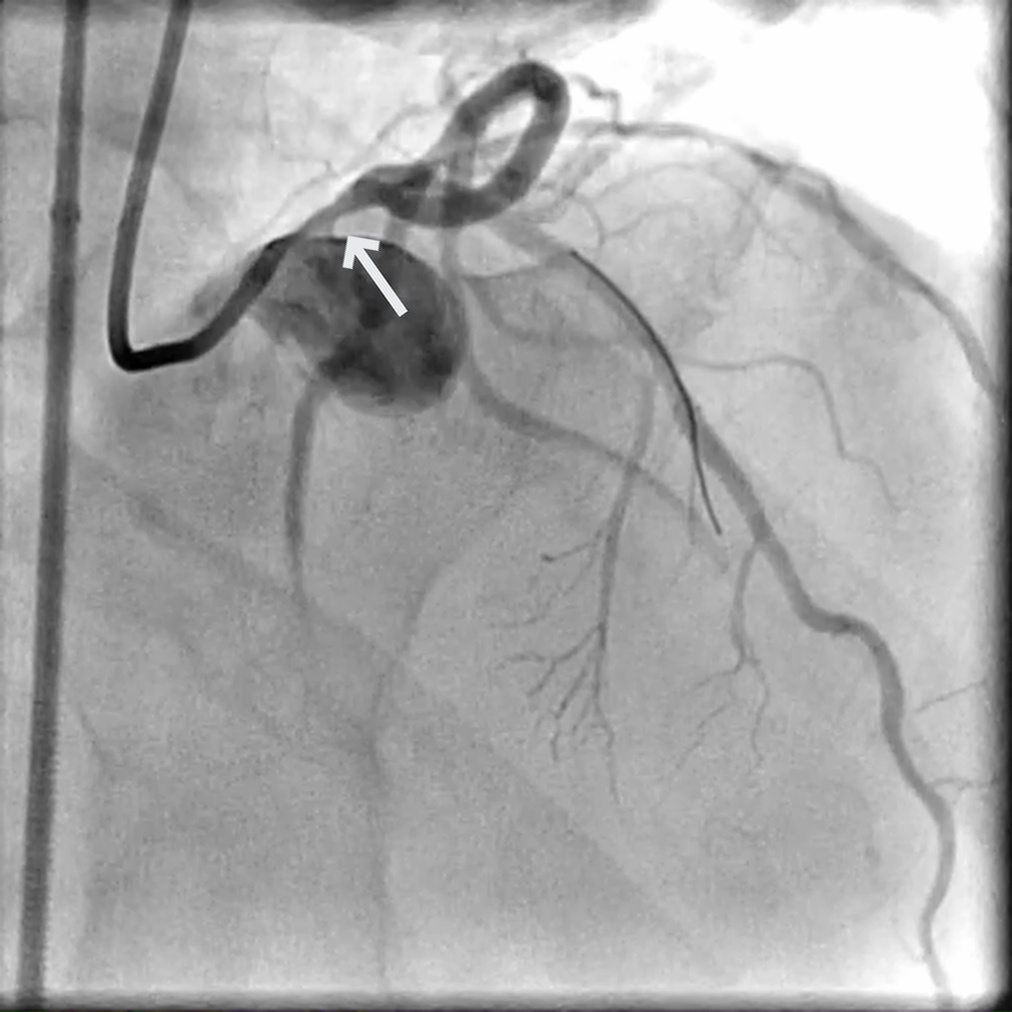

A 74-year-old male with multiple CAD risk factors presents with dyspnea on exertion, fatigue, and weakness.